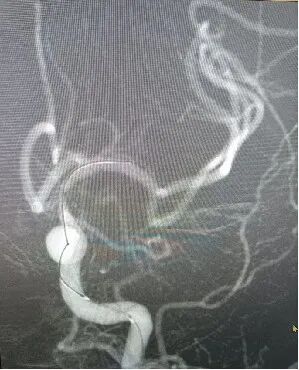

释放后造影。

植入后造

导丝怎么扩【载药时代 球扩天下】NOVA DES®颅内药物洗脱支架在颈内动脉颅内段重度狭窄的应用两例!滕州市中心医院&山西医科大学第二医院_https://www.jmylbn.com_新闻资讯_第21张

图像放大。

5.然后沿微导丝将赛诺神畅 NOVA DES®颅内药物洗脱支架系统送至病变部位定位后以8atm扩张后准确释放,释放后残余狭窄10%。